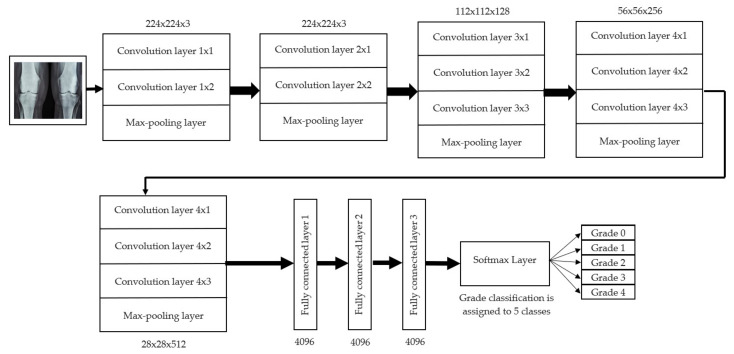

For knee RA severity classification, we conducted this research using a modified version of the VGG16 architecture and a domain adaptation technique, as shown in Figure 3. The VGG16 model was made up of five convolutional layers, three max-pooling layers, and three fully connected layers—all the digital X-radiation images needed to be resized to (227 × 227 × 3). In our implementation, X-radiation image information for training purposes accounted for eighty percent of the total, while X-radiation image information for evaluating purposes accounted for twenty percent. Although there are sixteen layers in VGG16, only a subset of those layers is required for feature extraction. In order to shorten the amount of time needed for training and establish more control over the fitting process, we assigned a dropout ratio value of 0.5 to the completely connected layer (fcl6) and the fully connected layer (fcl7). The characteristics were taken from the fully connected layers designated fcl6 and fcl7, respectively. To categorize the retrieved features into 1000 categories, VGG16’s architecture used a fully connected layer (fcl8). Then, we conducted one last round of tuning on the pre-trained VGG16 model’s ability to classify RA by changing parameters in the model’s last three layers. The model’s last three layers were swapped out for a fully linked layer, a softmax layer, and a classification layer. In addition, a newly linked layer was assigned to five groups of RA grades for the dataset: Grade 0, Grade 1, Grade 2, Grade 3, and Grade 4. We trained the proposed network by using digital knee X-radiations, a small-batch test dataset, gradient descent, and maximal epochs. Our proposed network learning strategy used stochastic gradient descent, and we compared its performance to previous efforts. The proportion of knee X-radiation images from the test set for which the network correctly predicted the RA grade was used to calculate proposed work accuracy. The proposed approach achieved an overall accuracy of 99.10% in classifying knee RA cases. Table 5 illustrates the Visual Geometry Group (VGG16) CNN operation for RA grade classification. Figure 4, depicts the RA classification using VGG16 architecture.